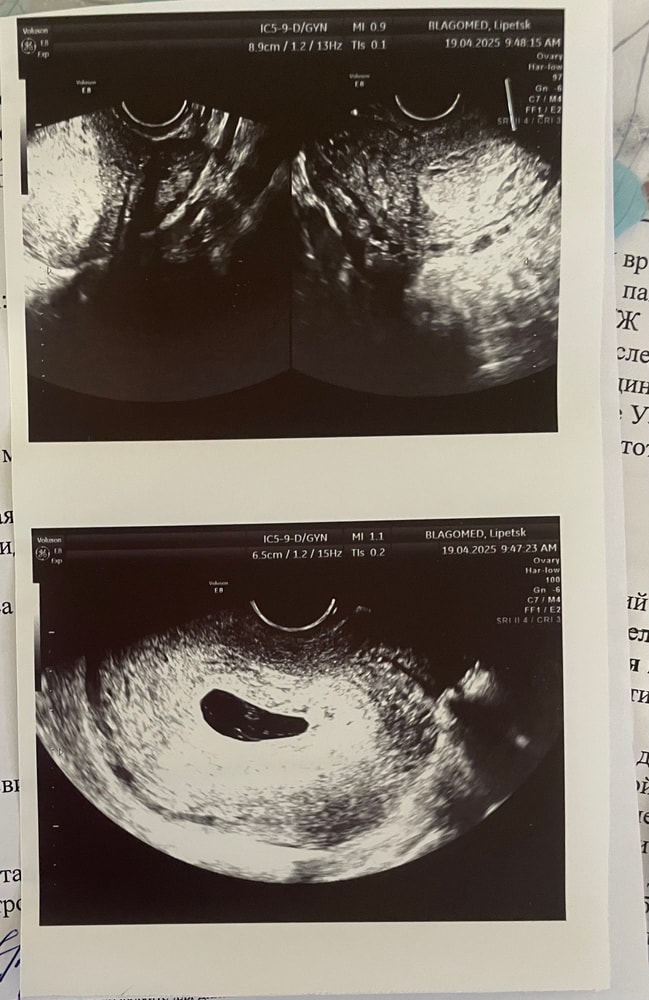

Пя в регресс уже пошло,срок у вас большой,у вас же ещё в середине марта хгч положительный был,значит овуляция в начале марта была и уже срок около 9 недель по УЗИ должен быть и эмбрион около 20 мм

Анастасия , ну так по месячным у вас же не 9 недель,а в значке стоит 11 неделя уже,с учётом поздней овуляции у вас по узи 8-9 недель должно быть уже,на таком сроке уже нет разницы даже с суперпоздней

Точно не развивающая, к сожалению. На таком сроке уже эмбрион должен быть и никак иначе

Хгч вырабатывает не эмбрион, а хорион. К сожалению, большие размеры ПЯ уже, всё уже должно быть видно. И то, что жм было и не перестал быть и есть регресс ПЯ тоже говорит о замершей